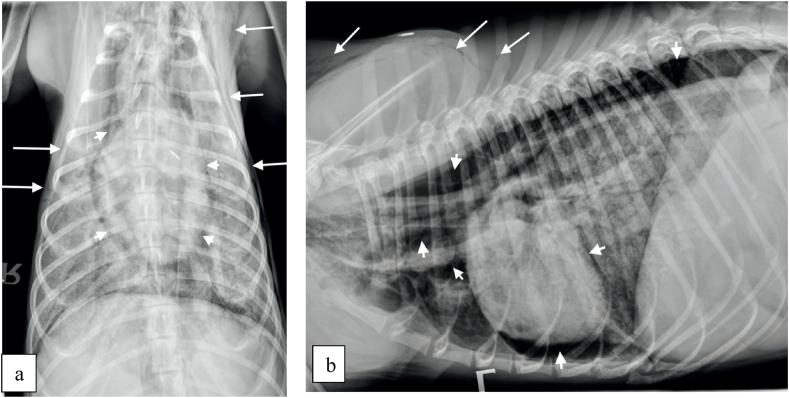

A 10-month-old lurcher with history of recurrent skin problems, presented with tachypnoea which had progressively become severe. Investigations included haematology, serum biochemistry, blood coagulation profile, diagnostic imaging, bronchoscopy and bronchoalveolar lavage (BAL). Cytological evaluation of the BAL revealed the presence of Pneumocystis cysts. The patient was euthanased on humane grounds prior to treatment against Pneumocystosis. To the best of our knowledge this is the first case of Pneumocystosis in a lurcher puppy.

一只10个月大的格力犬,有反复出现皮肤问题的病史,出现了逐渐加重的呼吸急促症状。检查包括血液学、血清生化、凝血指标、诊断性影像学、支气管镜检查和支气管肺泡灌洗(BAL)。BAL的细胞学评估显示存在肺孢子虫囊肿。在针对肺孢子虫病进行治疗之前,出于人道考虑对该患者实施了安乐死。据我们所知,这是首例格力幼犬患肺孢子虫病的病例。